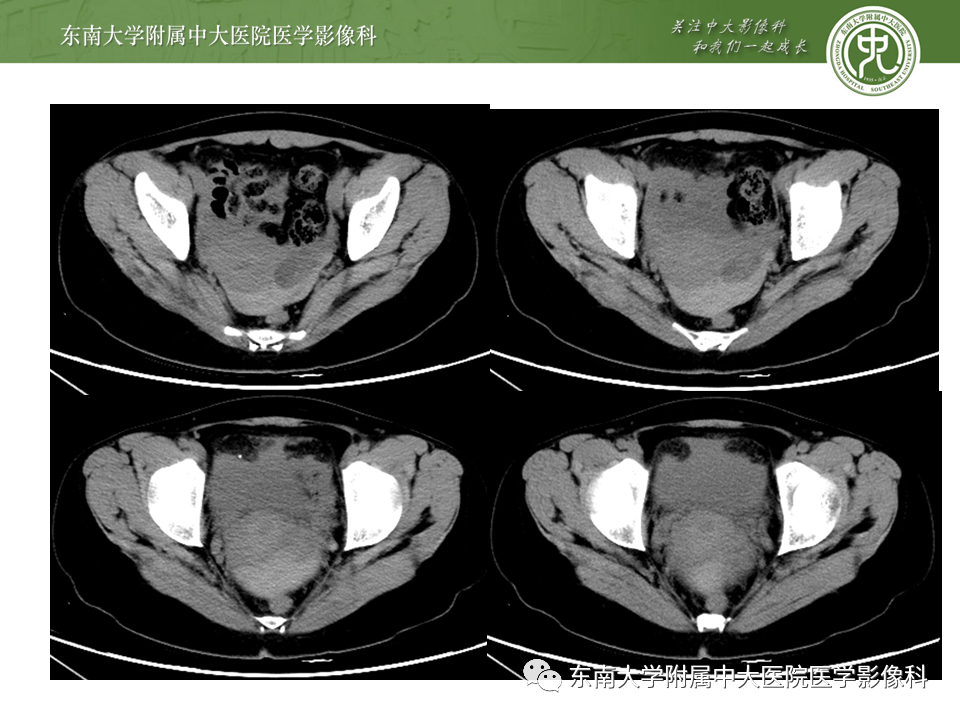

病史

女,24岁,因“停经42天,下腹痛3小时”入院

影像学表现